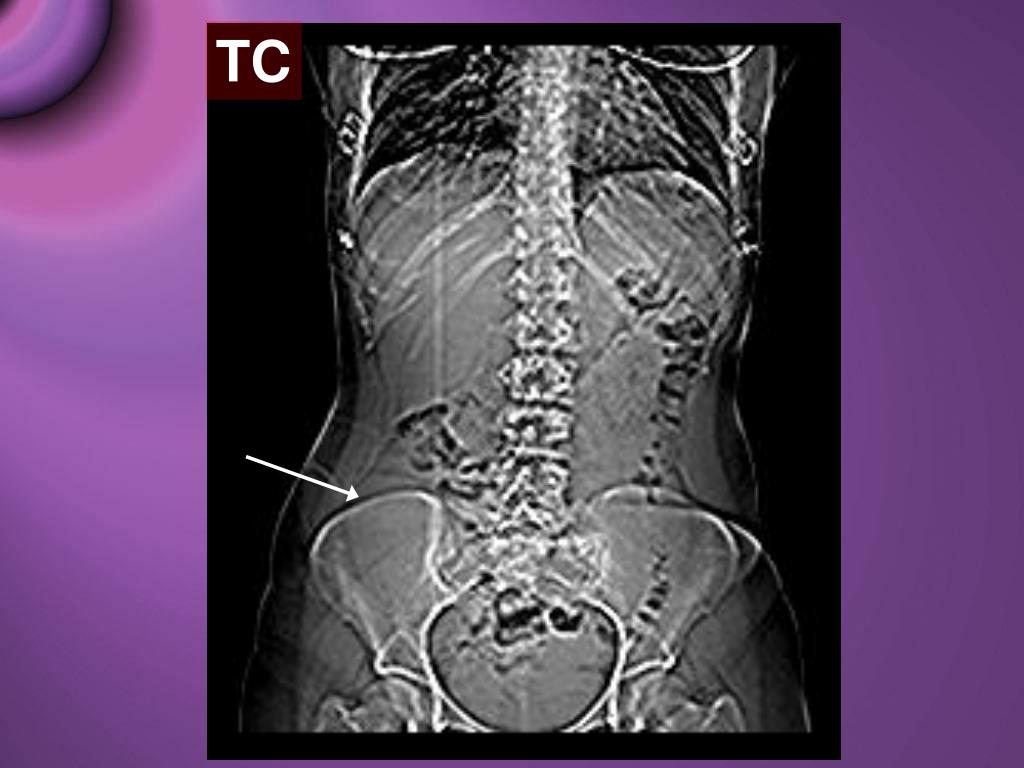

WebLa fosa del ilion puede presentar dolor de manera directa, principalmente por la instauración de procesos degenerativos, como es el caso de la osteoartrosis, pero debido a que. WebLa presencia de dolor en la fosa ilíaca derecha puede ser signo de algún problema sanitario, como puede ser la apendicitis. De todos modos, al igual que ocurre con la. Webfosa iliaca derecha en mujeres de 15 a 30 aÑos de edad estudio a realizarse en el hospital general martin icaza desde 1 de enero hasta el 31 de diciembre 2015 trabajo de. WebCausas del dolor de la cresta ilíaca. Músculos débiles. Si los músculos del abdomen y de la espalda inferior son demasiado débiles, la cresta ilíaca se puede ver afectada,. WebEl dolor abdominal agudo localizado en la fosa ilíaca derecha (FID) es uno de los principales motivos de consulta por dolor tras el traumático en las urgencias. WebMujer de 21 años, sin alergias medicamentosas ni antecedentes de interés, nuligesta, remitida desde atención primaria por dolor abdominal brusco de hora y media de. WebIntroducción. El dolor agudo en fosa ilíaca derecha (dFID) representa un problema diagnóstico, ya que puede englobar diferentes causas, y a veces es difícil tomar una. Webmedia y profunda en la fosa iliaca derecha, con signos de McBurney, Rovsing, Lanz, Capurro, Psoas, Obturador, Von Blumberg y talopercusión positivos; perístasis.

Webcon presencia de dolor abdominal tipo cólico, 8/10 EVA, en fosa iliaca derecha, sin irradiaciones ni exacerbaciones, el cual se acompañaba de náusea, llegando en 2. WebIntroducción. El dolor en la fosa ilíaca izquierda (FII) es un motivo de consulta muy frecuente en la práctica clínica habitual, suponiendo un reto diagnóstico. En su origen, podemos. WebDolor en fosa iliaca derecha, con migración previa, asociado a signos de respuesta inflamatoria como fiebre y desviación izquierda, por lo que se trata de un cuadro.

WebIntroducción. El dolor agudo en fosa ilíaca derecha (dFID) representa un problema diagnóstico, ya que puede englobar diferentes causas, y a veces es difícil tomar una. Webmedia y profunda en la fosa iliaca derecha, con signos de McBurney, Rovsing, Lanz, Capurro, Psoas, Obturador, Von Blumberg y talopercusión positivos; perístasis. WebEl dolor de la fosa ilíaca derecha (FID) puede ser motivo de alarma, ya que es un signo de una serie de condiciones de salud tales como la apendicitis. Como la mayoría de los.